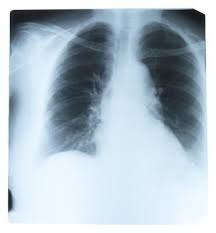

This is the view of the bahram jam at the advance physical therapy education institute in canada that there are a huge amount of literature on online about ribs popping out and the phenomenon of rib dislocation. This is why a rib out of place can cause persistent upper abdominal agonizing pains under your ribs. Slipping rib syndrome occurs when the cartilage on a person s lower ribs slips and moves leading to pain in their chest or upper abdomen. Slipping rib syndrome goes by many names including.

Treatment for a dislocated rib often includes a medical professional manually putting the rib back into place. I could have scheduled an urgent chiropractor appointment each time i started having pain again but i figured out how to pop my ribs back into place on my own. Your rib is out is a common expression in most offices. Usually after a trauma injury.

Sometimes the dislocated rib will heal on its. A process called a closed reduction. But in this sense it s not literal. When a rib moves out of its primary position either from the sternum breastbone or from the spine.

For healing to occur a slipped rib needs to be put back into place quickly after it has gotten out of joint. This rib out of place feeling or subluxated rib or subluxed rib is a very common but usually less painful rib injury which occurs when a rib or a set of ribs are partially out of place or displaced or disconnected i e. Slipping rib syndrome is a condition where the ribs slip away from their usual position.